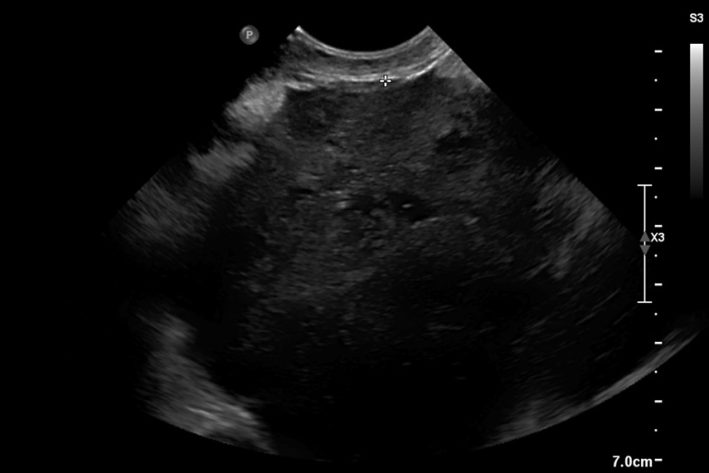

Mittels Ultraschalluntersuchung kann die Veränderung des Milzgewebes dargestellt werden. Im Frühstadium zeigt sich meist nur eine lokale Veränderung von Milzgewebe, sodass eine deutliche Masse abgegrenzt werden kann. Im fortgeschrittenen Stadium ist jedoch eine Zuordnung zur Milz nicht immer zweifelsfrei möglich. Eine Aussage darüber, ob es sich um eine gutartige oder bösartige Veränderung von Gewebe handelt, kann mittels Ultraschalluntersuchung nicht getroffen werden. Der Ultraschall erlaubt zusätzlich, die anderen Bauchorgane hinsichtlich Metastasierung zu untersuchen. Da Hämangiosarkome immer wieder einmal in den rechten Vorhof des Herzens metastasieren, sollte auch ein Herzultraschall durchgeführt werden.

Sollte sich freie Flüssigkeit im Bauchraum befinden, kann diese ultraschallgestützt punktiert und somit festgestellt werden, ob es sich um eine Blutung handelt.

Darstellung eines Milztumors im Ultraschall